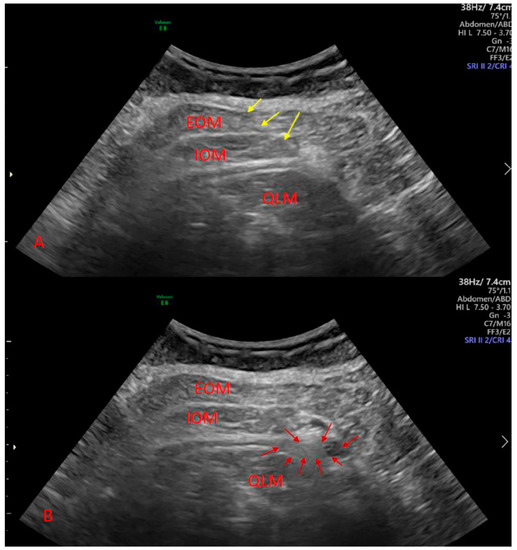

2.2. Procedure